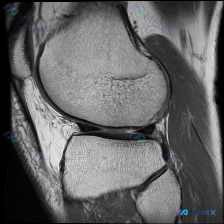

本次读片是膝关节MRI轴位T2加权图像,扫描层面为髌股关节层面:

- 骨骼:髌骨及股骨髁形态完整,骨皮质、骨髓信号未见异常

- 软骨:髌骨关节面软骨信号不均匀,髌骨外侧关节面可见明确信号异常,局部软骨变薄、表面不平整,T2加权像信号增高

- 关节腔:髌上囊及髌股关节间隙可见明显高信号积液,量较大

- 滑膜:外侧隐窝可见滑膜皱襞增厚、轻度滑膜增生表现

- 其他:股骨滑车软骨表面基本完整,周围软组织未见明显异常肿块或弥漫水肿,无急性骨折或侵袭性骨病变